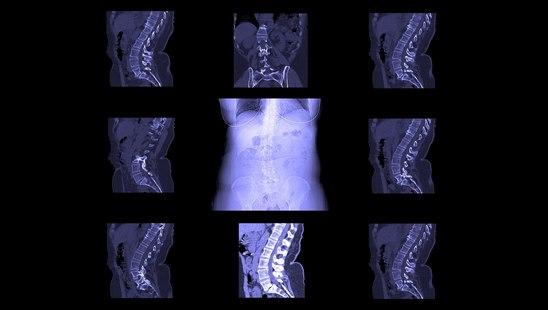

CT av ryggen

CT av ryggen benyttes ofte ved mistanke om sykdom eller skade i ryggen som trykker på nervevevet, særlig om det overveies operasjon.

CT bilder er svarthvite. Organene fremstilles i ulike grader av grått. Vev med lav tetthet, f.eks. luftfylte hulrom, vises som mørke eller svarte partier. Vev med høyere tetthet vises i lysere gråtoner. Jo høyere tetthet, jo lysere. Beinvev fremstilles hvitt.

CT av ryggen tas ved mistanke om sykdom eller skade i ryggen som trykker på nervevevet, og særlig i de tilfellene hvor det overveies operasjon eller man trenger resultatene raskt. CT tas også ved uklare ryggplager der f.eks. røntgen har gitt utilfredsstillende avklaring. MR er i mange sammenhenger en bedre undersøkelse enn CT, men CT er i mange tilfeller et godt nok alternativ (f.eks. om det er lang ventetid på MR). CT av ryggen brukes også i utredningen av bruddskader. Derimot foretrekkes MR og eventuelt scintigrafi i utredningen av svulster og kreftspredning til ryggen.

Redusert høyde på mellomvirvelskivene skyldes som regel slitasje eller skade på mellomvirvelskiven. Dersom skiven har sprukket, vil noe av innholdet kunne presses ut gjennom sprekken, det foreligger et prolaps. CT kan fremstille slike prolaps og kan synliggjøre om prolapset trykker på nerver eller ryggmarg. Det har vist seg at MR gir bedre bilder av prolaps, og denne undersøkelsen foretrekkes i dag dersom det er mulig å få utført den.

Sammenfall av ryggvirvel er at annet funn. Høyden på ryggvirvelen er redusert. Årsakene kan være skader, beinskjørhet, betennelse, spredning av kreft, svulster. Slike funn kan kreve videre utredning med MR, som også bedre kan vise mulige skader på nervevevet.

Ryggskader undersøkes som regel først med røntgen for å se etter brudd i ryggen. CT er nyttig ved store skader og viser utstrekningen av eventuelle brudd. CT kan også avsløre brudd som gir ustabile forhold i ryggsøylen. Eventuelt kan CT identifisere beinsplinter i ryggmargskanalen som må fjernes kirurgisk. MR er ikke like velegnet som CT ved akutte ryggskader, men kan avdekke blødninger og knusningsskader av ryggmargen.